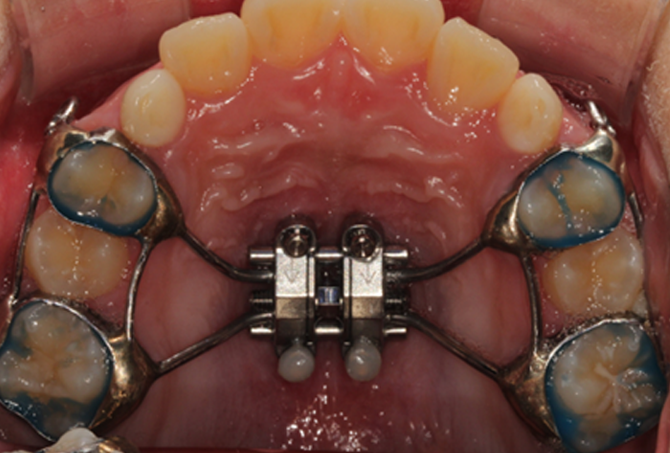

설측교정은 치아 안쪽(설측면)에 초소형 장치로 보이지 않게

아름다운 미소를 만드는 고난이도 프리미엄 교정 치료입니다.

난이도가 높은 만큼 풍부한 진료 경험이 중요합니다.

강남에서 다년간 설측교정에 특화된 경험을 바탕으로,

3D 디지털 기술을 활용한 맞춤 설계, IDBS방식을 통한

정밀하고 불편감 없는 치료를 제공합니다.

• STEP 02 설측 맞춤형 브라켓 지그 제작

교정전문의와 CAD/CAM전문가의 디자인으로

개별적인 설측 지그를 제작합니다.

• STEP 03 장치 부착 및 치료

IDBS(간접부착)방식을 이용하여

정밀한 위치에 장치를 부착합니다.